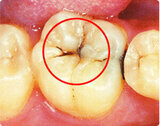

保険適用で白い詰め物を使用するには、治療部位や症例に関する一定の制約があります。具体的には、患者が虫歯の治療を必要としている部位が、目立つ前歯であることが大前提となります。また、治療の程度が「軽度から中等度の虫歯」である必要があり、重度の虫歯では適用されないこともあります。